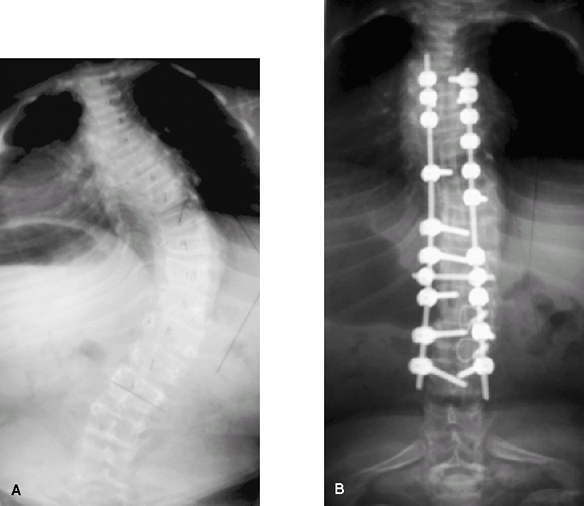

New instrumentation methods are changing the approach to scoliosis in OI (7) (Fig. 3).

-

Curves may be fused early (at 40°) to

halt the relentless progression; this procedure is important in

maintaining function and in preventing respiratory complications.

Fig. 3. Scoliosis in osteogenesis before (A) and after (B) surgical correction with rods and screws.